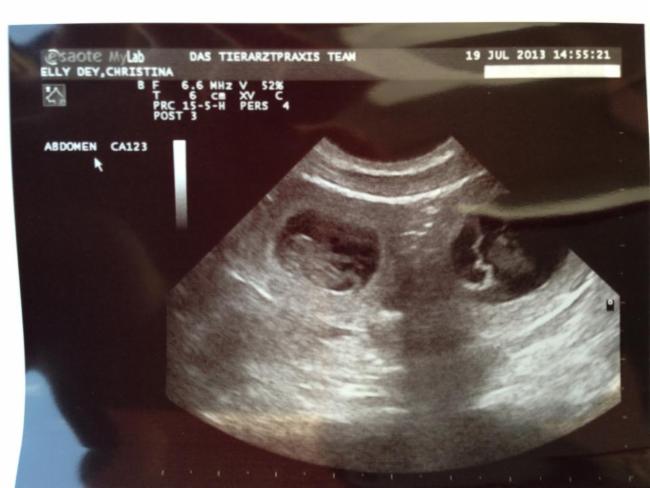

4. Woche | Am 22. Tag sind die Embryonen sichtbar. Der Herzschlag kann zur Diagnose der Trächtigkeit herangezogen werden. Anstrengende Aktivitäten sind jetzt zu vermeiden.Die Proteinzufuhr im Futter kann erhöht werden. Hierfür eignet sich sehr gut die Gabe von Welpenfutter. Zu diesem Zeitpunkt kann mit einer Ultraschalluntersuchung der Zustand der Trächtigkeit festgestellt werden. Besprechen Sie mögliche Risiken einer solchen Untersuchung mit dem Tierarzt. |

Do, 18.07.2013 bis Mo, 22.07.2013 | Dies ist der beste Zeitpunkt, um die Trächtigkeit anhand des Herzschlags zu diagnostizieren. Die Embroynen sind etwas walnussgroß und sind gleichmäßig im Uterus verteilt. |